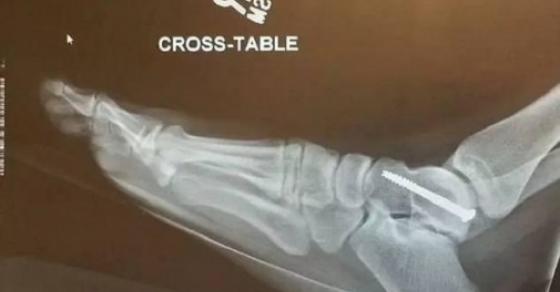

Audra đã không mua bảo hiểm y tế, nên cô đã mất nhiều thời gian và tiền bạc cho việc chữa trị. Khi xuất viện, do có nhiều vết nứt nên mắt cá chân, mông, đầu gối của cô đều được gắn bằng những ốc vít.